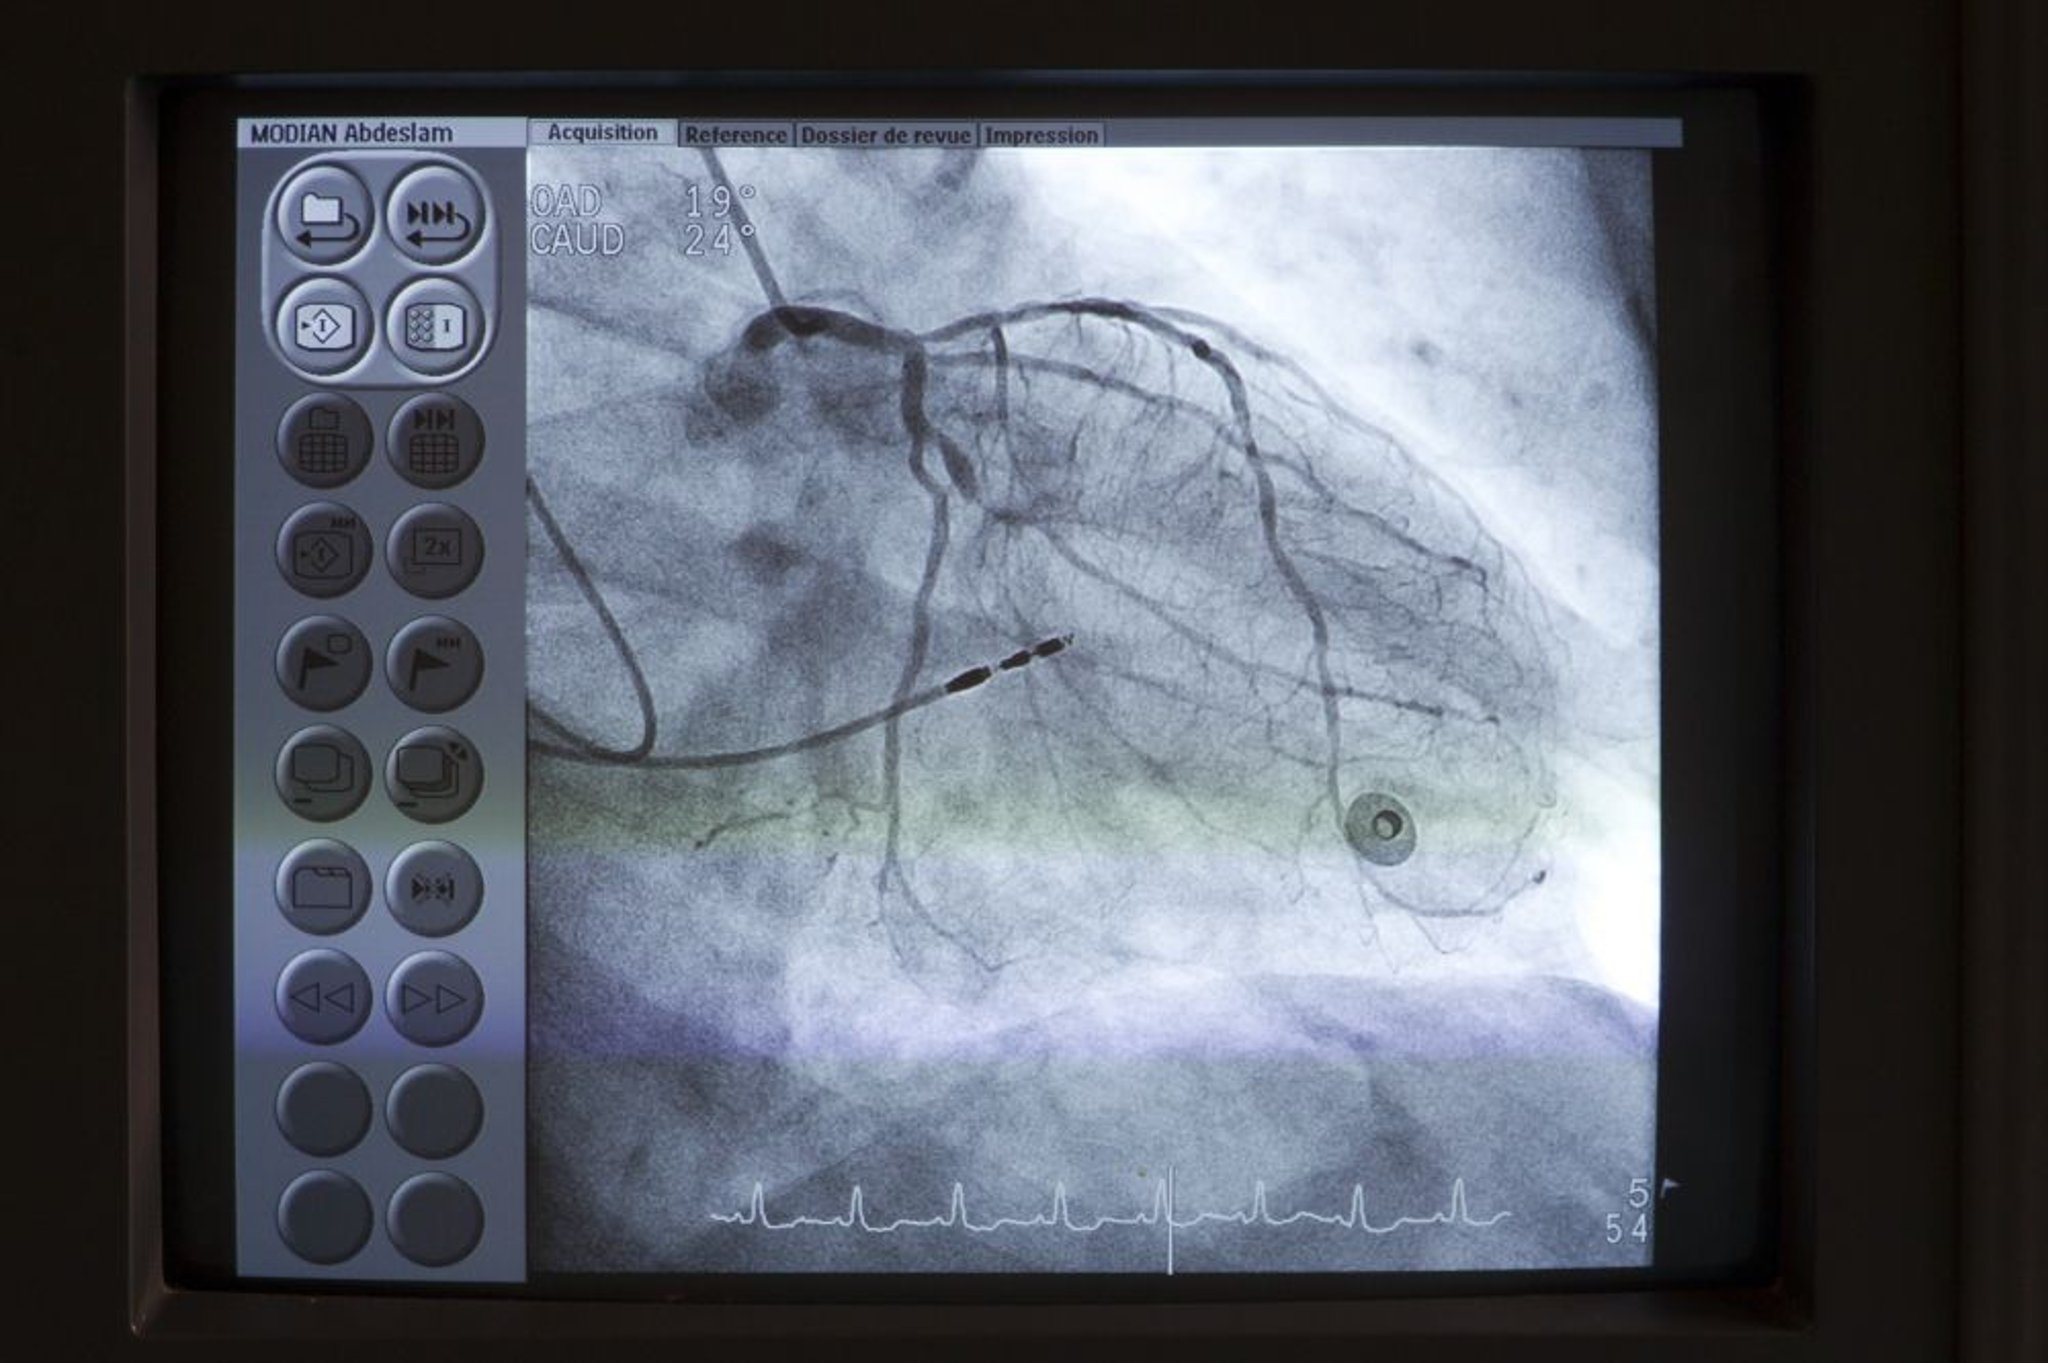

Coronarographie

Un cathéter (en haut à gauche) est placé au niveau de l'ostium du tronc commun coronaire gauche. Le produit de contraste est ensuite injecté dans les artères coronaires sous radioscopie pour détecter des anomalies telles que des sténoses.

Astier/BSIP/SCIENCE PHOTO LIBRARY